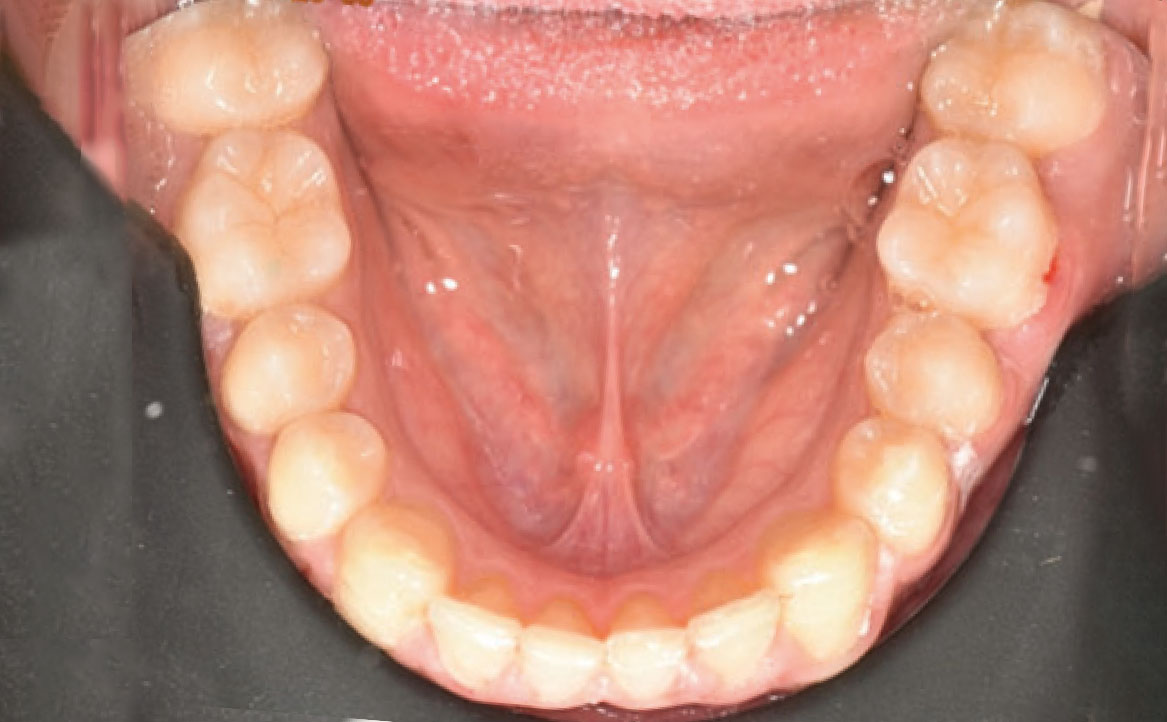

Il paziente si è presentato per la sua prima visita presso il reparto di Odontoiatria e Protesi Dentaria dell’Ospedale Vita-Salute San Raffaele diretto dal prof. E. F. Gherlone. All’esame obiettivo era evidente una malocclusione scheletrica e dentale di classe II associata a morso profondo e lieve affollamento anteriore superiore. In particolare, sono stati segnalati: rapporti occlusali di classe II, morso profondo, perdita di overjet, contrazione dell’arcata superiore e inferiore con leggero affollamento (fig. 1a-f). La richiesta del paziente era quella di migliorare l’estetica dei denti anteriori con allineatori invisibili di tipo Invisalign. Tuttavia, sia il paziente che il genitore sono stati informati che, per ragioni di efficacia e risoluzione del problema, era necessario agire anche a livello di funzionalità e risoluzione della malocclusione.

In primo luogo, sono stati prescritti entrambi gli esami radiografici ortodontici: OPT e teleradiografia latero-laterale del cranio (fig. 2a-b). Successivamente, in accordo con il genitore, è stata concordata una terapia ortodontica in due tempi. L’inizio della terapia è stato effettuato con Carriere Motion ed elastici di classe II, con l’obiettivo di migliorare la classe molare (fig. 2c-e).